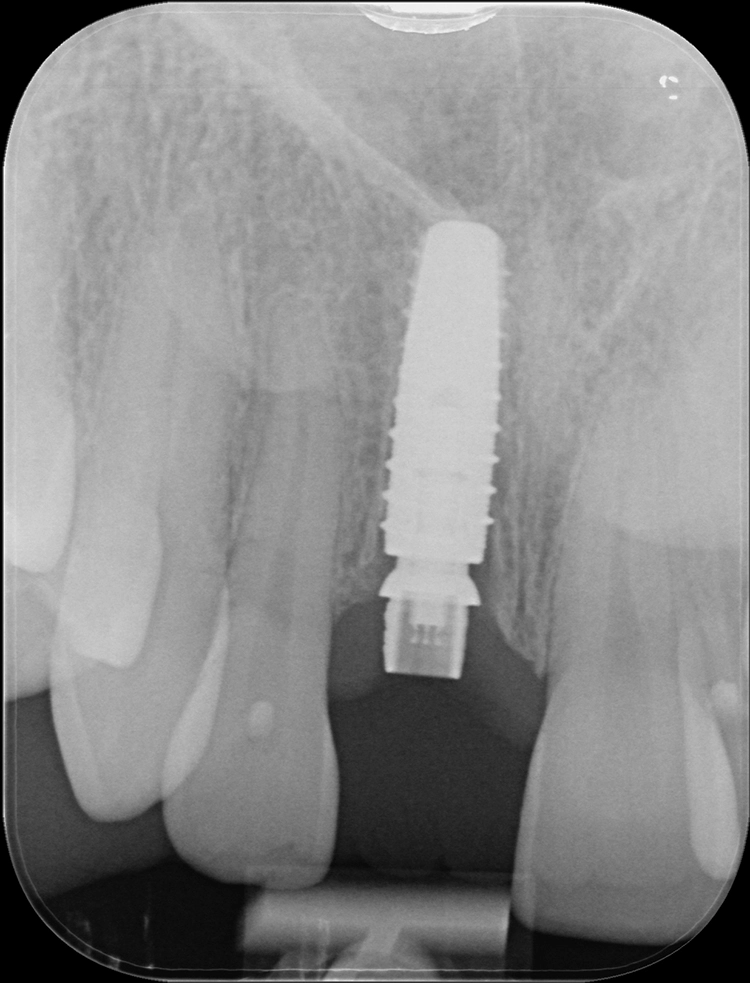

Die Alveole wird von Granulationsgewebe gesäubert und direkt postoperativ durch ein Kleinröntgen auf Wurzelreste kontrolliert. Die Aufbereitung des Implantatbettes und die Implantatinsertion erfolgt im apikalen Bereich tendenziell eher palatinal. Im Bereich der Implantatschulter wurde ein Abstand von 2,5 mm zur vestibulären Lamelle eingehalten.

Besonders zu beachten ist auch die dreidimensionale Positionierung des Implantates. Eine zu weit vestibuläre Positionierung der Implantatschulter ist auf jeden Fall zu vermeiden, ebenso sollte die Implantatschulter in koronal-apikaler Richtung knapp unterhalb der vestibulären Knochenkante zum Liegen kommen, um Umbauprozesse von 0,5 – 1 mm in diesem Bereich zu kompensieren. Zwischen dem Implantat und der inneren vestibulären knöchernen Wand sollte ein 1,5 – 2,5 mm „Jumping Gap“ bestehen [16,17].

Dieser Spalt dient der Ausbildung eines Blutkoagels, welches durch ein passgenaues, individuelles Provisorium immobilisiert wird. Auch wird die angrenzende Gingiva während der Heilungsphase durch das Provisorium in der Position gestützt.

Während der Osseointegration des Implantates sollten keine Bewegungen auf das Implantat übertragen werden, daher ist es wichtig, die Okklusion entsprechend einzustellen und hier vor allem auch ein Auge auf die dynamischen Grenzbewegungen zu haben. Die Patientin wird angewiesen, den Zahn die nächsten acht Wochen möglichst zu schonen.